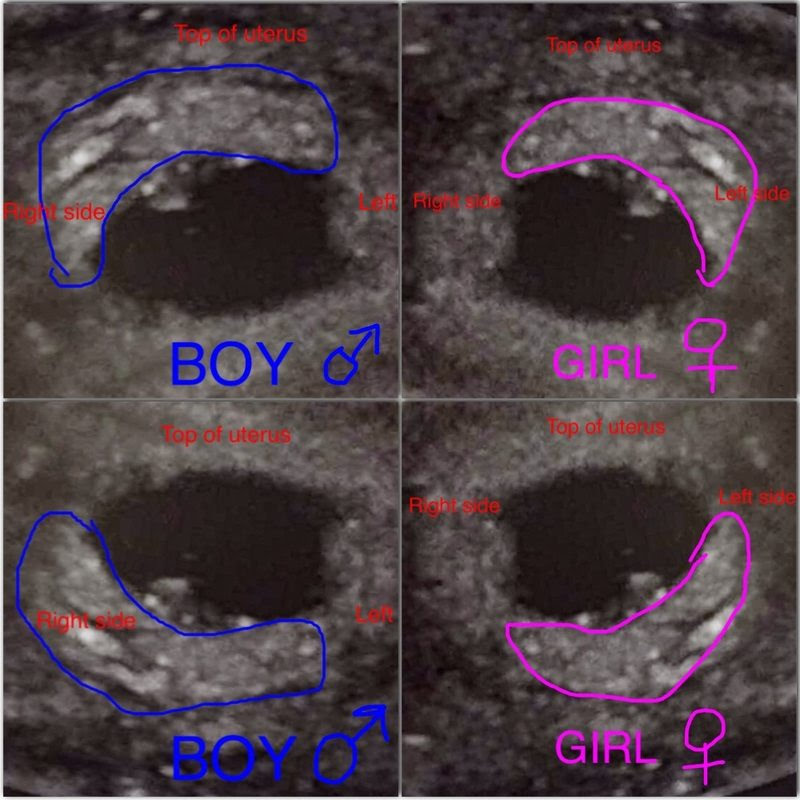

نظرية رامزيوهي طريقة طُورت من قبل الدكتور سام رامزي، ويُشار إليها باسم طريقة رامزي لتحديد جنس الجنين. وتستخدم هذه الطريقة مكان المشيمة كعلامة للكشف عن جنس الجنين؛ إذ يتم الكشف عن مكان المشيمة باستخدام الموجات فوق الصوتية في الفترة بين الأسبوع السادس إلى الأسبوع الرابع عشر من الحمل. وإذا كانت المشيمة في الجانب الأيمن، فإن الجنين صبي، وإذا كانت في اليسار، فإنها فتاة.

من الممكن العمل بها وعمر الجنين خمس أسابيع الى ١٢ أسبوع